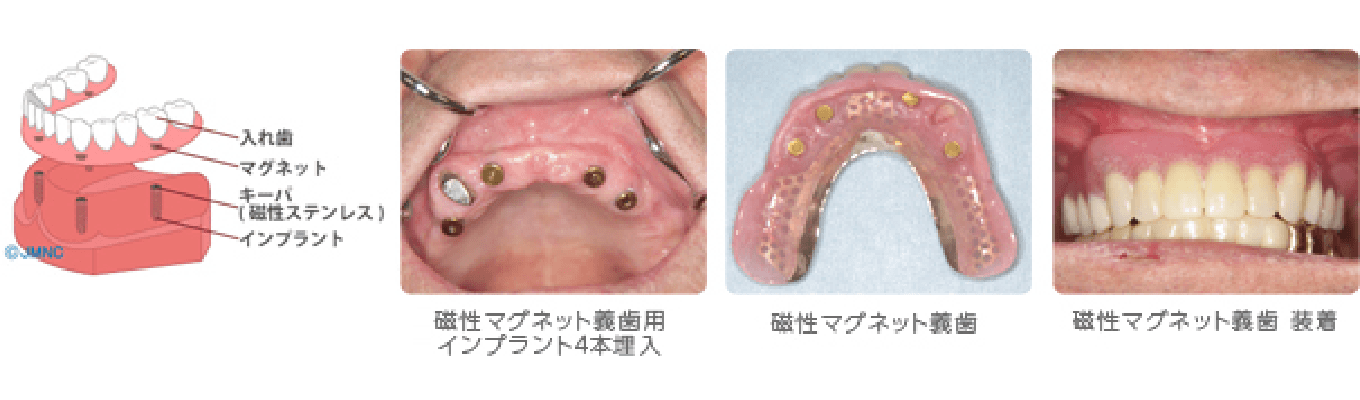

磁性アタッチメント用インプラント

総入れ歯や多数歯欠損の方で、アゴの骨がやせてしまい、入れ歯がずれたり、落ちたりする方におすすめです。磁石の力で入れ歯を固定します。